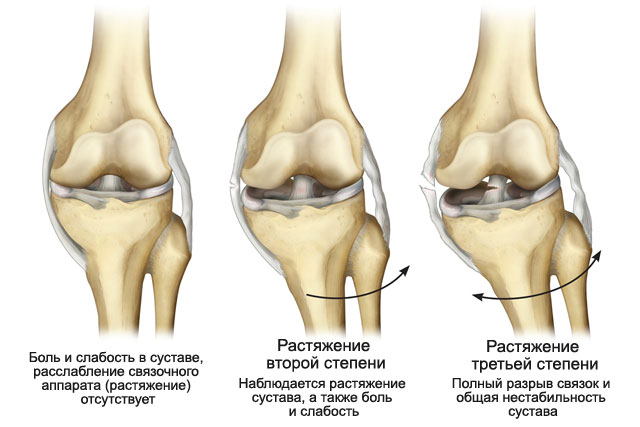

В зависимости от степени повреждения связок коленного сустава выделяют несколько форм тяжести:

- I степень — разрыв небольшого количества волокон;

- II степень — разрыв до 50% волокон;

- III степень — повреждение более 50% волокон.

Также различают уровни нестабильности, которые определяются расстоянием смещения бедренной и большой берцовой кости:

- легкая (до 5 мм);

- умеренная (от 5 до 10 мм);

- тотальная (от 10 мм).

При диагностировании последней стадии повреждения коленного сустава проводится замена на искусственный имплант.